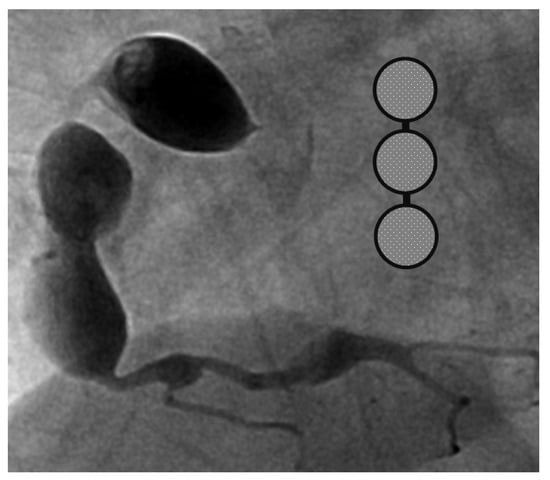

A 4-month-old infant girlwho presented with intermittent fever without explanation for 14 days was admitted.Laboratorydata revealed leukocytosis (19.5 × 109/L), high sensitivityC-reactive protein (CRP, 1139.04 nmol/L), and thrombocytosis (590 × 109/L). Negative culture reports were found in blood and urine. The empirical antibiotics administration did not achieve clinical improvement. The subcostal view of echocardiography andtransthoracic echocardiography (TTE) revealed three giant fusiform aneurysms of the proximal right coronary artery, along with other smaller aneurysms in the left coronary system. (Figure 1) Acute mitral insufficiency with moderate pericardial effusion was also present. The three beaded aneurysms were subsequently confirmed on a selective right coronary angiogram. (Figure 2) The fever resolved after receivinga high-dose intravenous immunoglobulin (IVIG) infusion. Aspirin with anticoagulant drugs (subcutaneous injection of low molecular weight heparin) administration was initiated and serial echocardiography as well as invasive coronary angiography follow-up were regularly performed sincethe giant aneurysm’s detection. (Figure 3) This report revealeda “beaded aneurysm” as a special medical image for KD.Itsfundamental nature of non-contiguous aneurysms could be a key to identifying antecedent KD vasculopathy compared toother coronary artery aneurysms. Written informed consent was obtained from the participant for the publication of this case report.

A pediatrician must check the echocardiography imaging of coronary arteries in infants with prolonged fever and evidence of elevated inflammation markers whenever the reasonable cause is absent because positive echocardiography findings were regarded as a set standard for acute KD accordingly. Coronary aneurysms can occur in up to 25% of KD children without a timely infusion of high-dose IVIG such as in this index case.As coronary aneurysms have become rare due to the widespread use of IVIG therapy for KD, beaded aneurysm is considered to be even rarer. There are no reports on the frequency of beaded aneurysms in KD, but it is presumed to be relatively rare.The final size of coronary aneurysms defines the future risk stratification generally speaking. In small or medium-sized aneurysms (<8mm or Z score <10), spontaneous regression of the aneurysms without significant cardiovascular sequela such as long-term luminal myofibroblastic proliferation is possible. In this case, the subcostal view of echocardiography and TTE revealed three giant fusiform aneurysms of the proximal right coronary artery, along with other smaller aneurysms in the left coronary system (Figure 1a–c). The three beaded aneurysms were confirmed by coronary angiogram is showed in Figure 2. In contrast with smaller aneurysms, giant aneurysms (>8 mm or Z score >10) seldom or never regress over time, which could be observed from the timeline of the index case(Figure 3).

Figure 1. Transthoracic echocardiology on the 16th months after illness of aneurysm. Three RCA aneurysms in a beaded arrangement from the subcostal view of echocardiography (a) and transthoracic echocardiogram imaging showed first with second RCA aneurysm (b) as well as first with third RCA aneurysm (c).